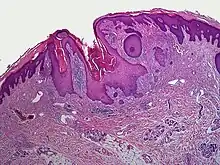

A dilated pore, also known as a dilated pore of Winer, is a cutaneous condition characterized by a solitary, prominent, open comedo on the face or upper trunk of an individual.[1]: 675 Louis H. Winer is credited with discovering the dilated pore. [2][3]